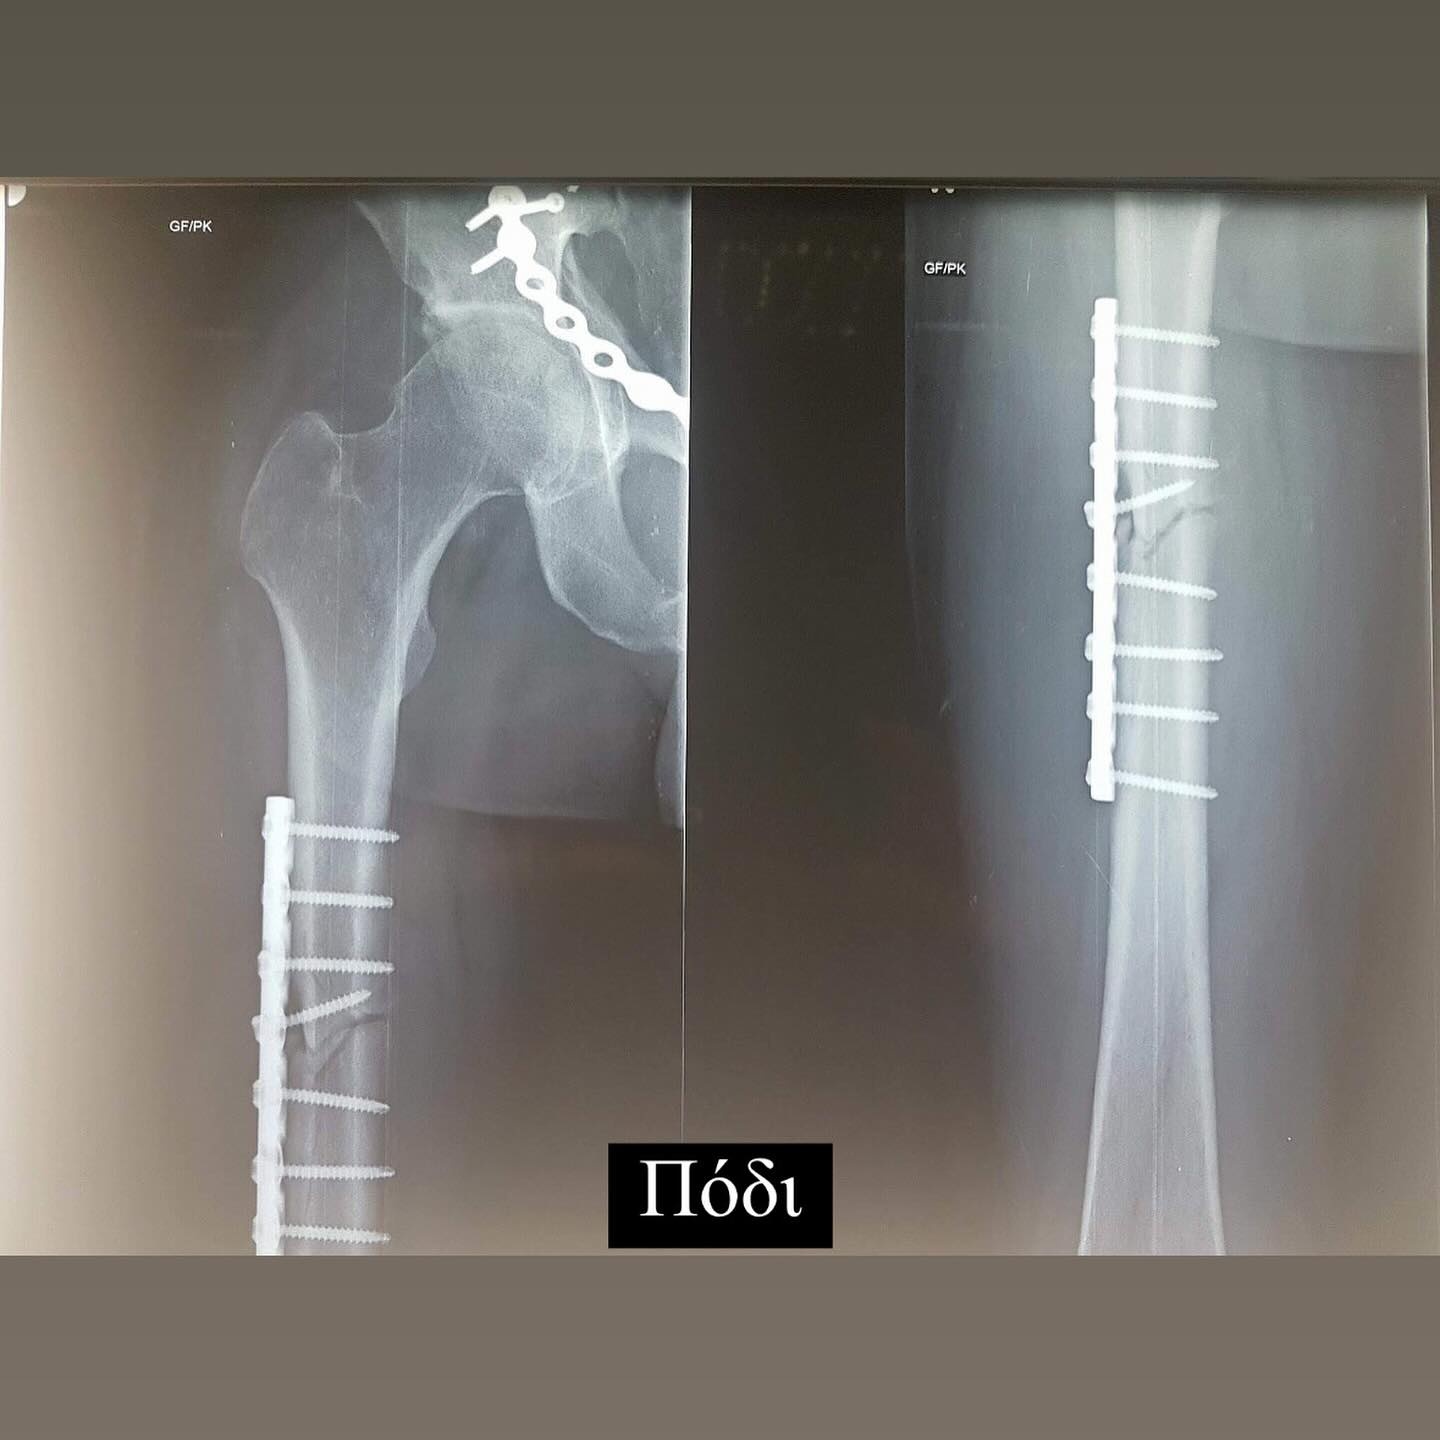

Σήμερα συμπληρώνονται 6 χρόνια από το τροχαίο ατύχημα που είχε ο Ηλίας Βρεττός και δημοσίευσε πρώτη φορά φωτογραφίες από τις ακτινογραφίες που του έκαναν και δείχνουν τα σίδερα που έχει σε χέρι, πόδι και λεκάνη. Συγκεκριμένα έγραψε ο τραγουδιστής: 19/02 Αγία Φιλοθέη μου Μεγάλη η Χάρη σου!!! Σ´ευχαριστώ… 6 χρόνια πέρασαν και όλα ακόμα μοιάζουν σαν χθες… Τα σίδερα μέσα μου που για πρώτη φορα σας δείχνω στα X-rays έτσι κι αλλιώς δεν με αφήνουν να ξεχαστώ. Όμως είμαι καλά και κυρίως είμαι εδώ!